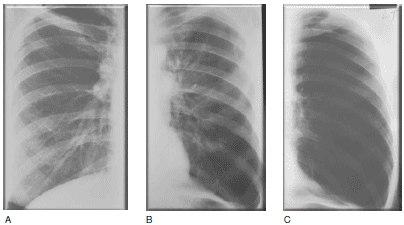

Рентгенография грудной клетки при хронической обструктивной болезни легких (ХОБЛ) у пациентов с бронхитическим фенотипом II (А), III (В) и IV (С) степени тяжести по данным спирометрии согласно классификации Международной инициативной группы по проблемам хронических обструктивных заболеваний легких (GOLD). От А к С заметно усиление легочного сосудистого рисунка по сравнению с нормой, ухудшение его четкости, появление извилистости и невозможность проследить ход сосудов от центра к периферии.

Рентгенография грудной клетки при хронической обструктивной болезни легких у пациентов с эмфизематозным фенотипом II (А), III (В) и IV (С) степени тяжести по данным спирометрии согласно классификации Международной инициативной группы по проблемам хронических обструктивных заболеваний легких (GOLD). От А к С заметна прогрессирующая утрата легочных сосудов. Можно видеть постепенное увеличение объема легочной паренхимы и уменьшение ее плотности.